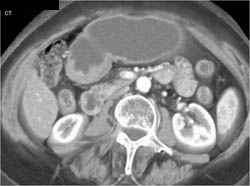

Antral Carcinoma